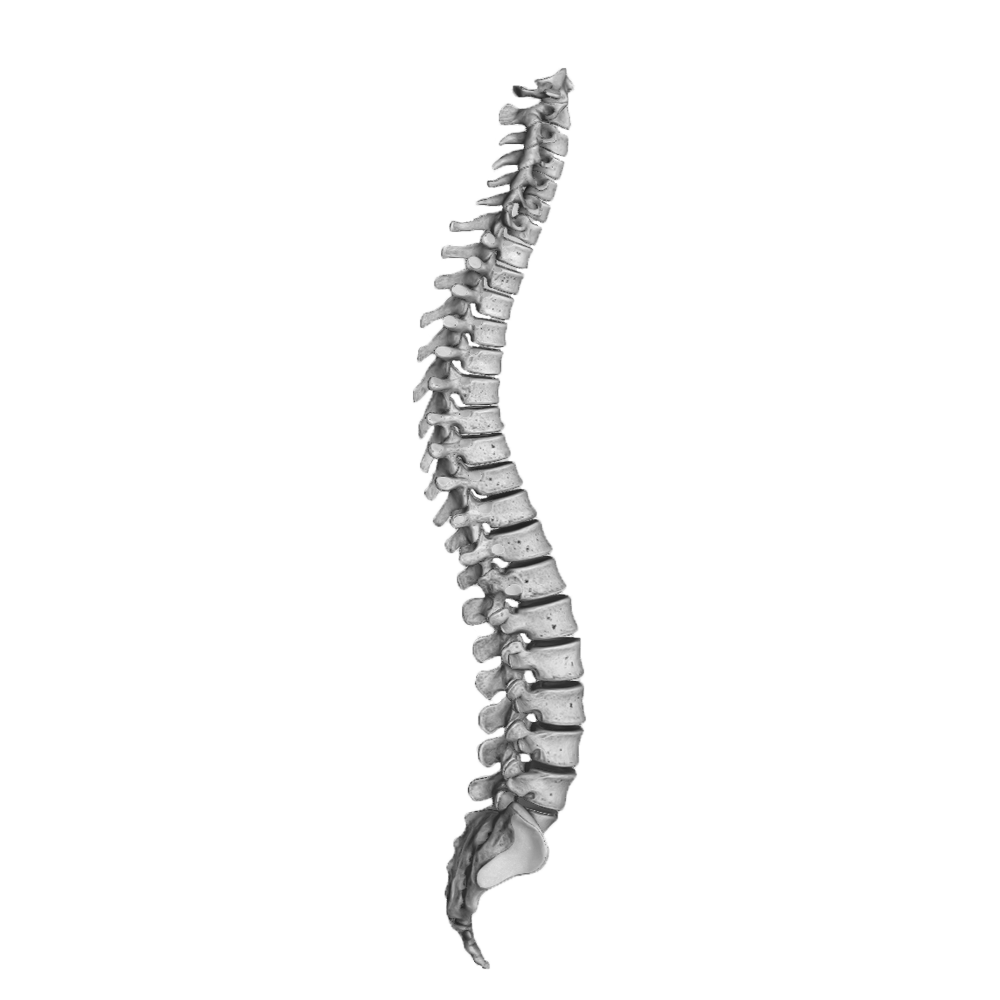

Kiropraktor

Kjeveteamets kiropraktor vil snakke med deg om din egen opplevelse av plagene, samt utføre ortopediske og nevrologiske tester i tillegg til å vurdere muskulatur i nakke og kjeve for å stille riktig diagnose, og for å utelukke alvorlig sykdom. Muskelspenninger, slappe leddbånd, og redusert bevegelighet i kjevens og nakkens ledd er svært vanlige årsaker til TMD. Uvaner, overbelastning, stress og uheldig ergonomi på jobb, hjemme og i sosiale situasjoner er også kjente bidragsytere.